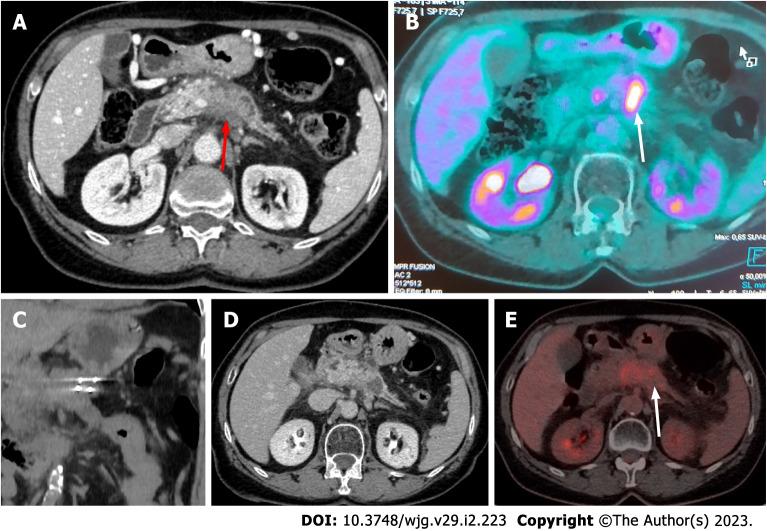

Pancreatic cancer is currently the seventh leading cause of cancer death (4.5% of all cancer deaths) while 80%-90% of the patients suffer from unresectable disease at the time of diagnosis. Prognosis remains poor, with a mean survival up to 15 mo following systemic chemotherapy. Loco-regional thermal ablative techniques are rarely implemented due to the increased risk of thermal injury to the adjacent structures, which can lead to severe adverse events. Irreversible electroporation, a promising novel non-thermal ablative modality, has been recently introduced in clinical practice for the management of inoperable pancreatic cancer as a safer and more effective loco-regional treatment option. Experimental and initial clinical data are optimistic. This review will focus on the basic principles of IRE technology, currently available data, and future directions.